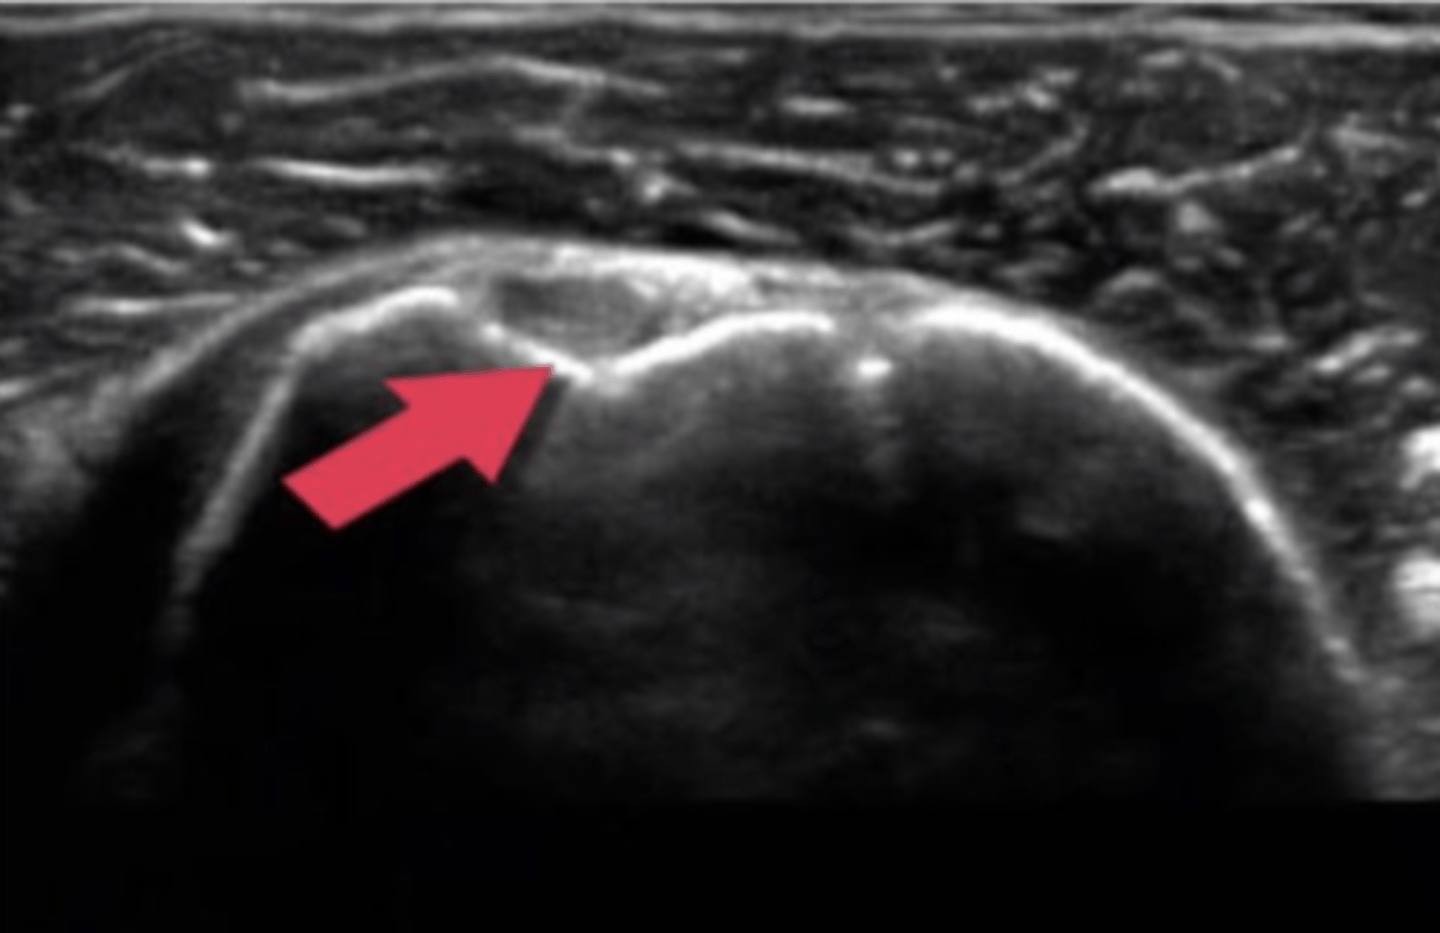

Ultrasound, partial tear

What type of imaging is this and what is identified by the white arrows?

a. CT scan, fracture

b. Ultrasound, partial tear

c. Ultrasound, Swollen Bursa

d. T2 MRI, torn ligament